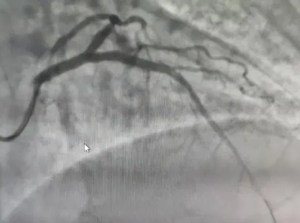

于前降支病變處

植入1枚支架

再次造影顯示

支架膨脹貼壁良好

血管通暢

患者轉危為安